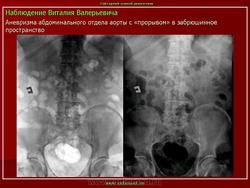

Наблюдение Tatarin

Женщина 77 лет. Жалобы на боли в животе. Пальпируется образование в околопупочной области живота. Аневризмы брюшной аорты и обеих общих подвздошных артерий.